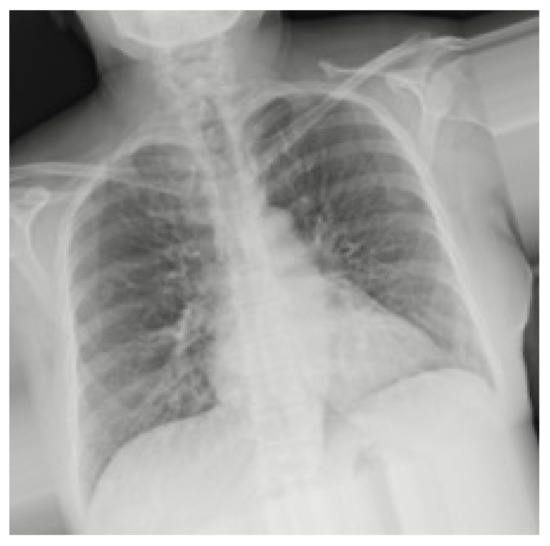

Although in Figure 1a,b the differences in lung health are obvious, with large white opacities in the infected lung, the differences between healthy lungs and lungs infected by COVID-19 are often much more subtle. Additionally, some other illnesses like pneumonia can appear similar in an X-ray to COVID-19, requiring intensive review to distinguish them from the latter virus. With cases drastically increasing each day, it can take a significant amount of time for doctors to analyze these X-rays that could be used for treating patients instead. Couple this with the tedious work of manually analyzing hundreds of images in a high stress environment and there is an even greater overburdening of doctors and risk of mistakes.

Figure 1.

X-rays of healthy and infected patients. X-rays from [7,8]. (a) Sample X-ray for healthy lungs. (b) Sample X-ray for COVID-19-infected lungs.